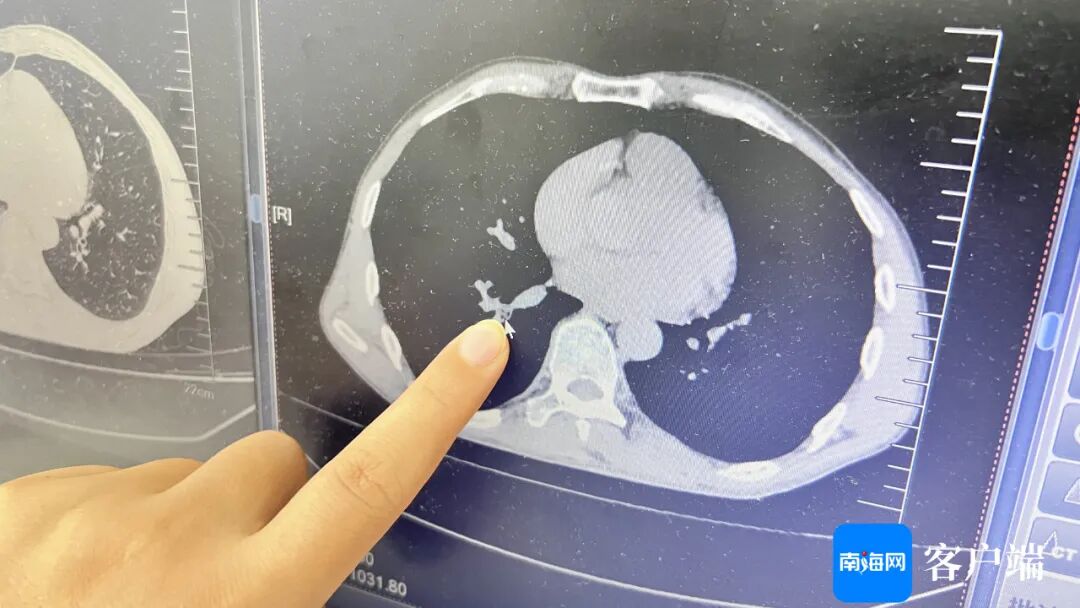

对此,林玲医生为患者做胸部CT检查,发现患者右下叶外后基底段有一块阴影,结合其病史,考虑是有异物。

“当时病人说很难受,就第一时间给他做了气管镜的术前检查,评估有没有这些禁忌证。”林玲表示,次日在局麻下为患者手术,术中非常清晰地看到有东西在支气管里,有翅膀的,异物被很多痰包裹着,吸了周围的痰后,暴露出了异物,就是一只蟑螂。